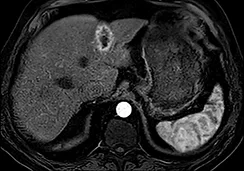

Imagerie de surveillance (figure 3)

La nécrose tumorale est visible lorsque la dose d’irradiation est élevée avec une destruction de la vascularisation tumorale. Mais la distribution inhomogène du traitement dans des lésions de grand volume rend l’interprétation radiologique difficile.

Tout d’abord une augmentation paradoxale de la taille de la tumeur peut être observée dans la phase initiale en raison de la nécrose et de l’œdème, elle est observée jusqu’à 36 % des lésions durant le 1er mois. Par conséquent, l’évaluation de la réponse tumorale doit être effectuée après 3 mois (98). La décroissance en taille de la lésion est très lente, avec une réponse complète et des critères d’amélioration qui augmentent avec le temps : dans l’étude de Lee et al., la réduction de la taille de la tumeur est de 2 % à 1 mois, 14 % à 3 mois, et 28 % à 6 mois (99). Bien que la diminution de la taille de la tumeur soit rassurante, l’absence d’augmentation dans le temps est un signe positif, et peut être considéré comme le reflet d’une réponse clinique, car l’histoire naturelle de la tumeur est la poursuite de la croissance tumorale…

Il est préférable d’utiliser les critères mRecist pour juger de l’efficacité du traitement (100), mais les variations du réhaussement tumoral, la diminution de l’hypervascularisation peuvent se faire attendre. Les données de Lee et al. montrent une amélioration selon mRecist dans 31 % des cas à 1 mois, 50 % à 3 mois et 59 % à 6 mois. Par conséquent, il faut attendre jusqu’à 3-6 mois avant de prendre la décision de retraiter, le meilleur signe de progression étant l’apparition de nouvelles lésions péritumorales ou à distance dans le foie.

| Acquisition en IRM à la phase artérielle et portale de l’injection d’un carcinome hépa- to-cellulaire de 8 cm de diamètre sur hépatopathie dysmétabolique chez un patient de 63 ans présentant une contre-indication formelle à la chirurgie en raison d’une myocardiopathie ischémique avec dysfonction ventriculaire contre-indiquant une prise en charge chirurgicale. | |